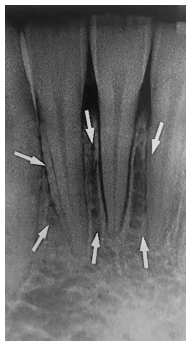

Analise a imagem radiográfica a seguir.

WHITE, S.C.; PHAROAH, M.J. Radiologia Oral: Princípios e Interpretação. 7. ed. Rio de Janeiro: Elsevier, 2015..

As estruturas anatômicas apontada pelas setas brancas correspondem à(ao)